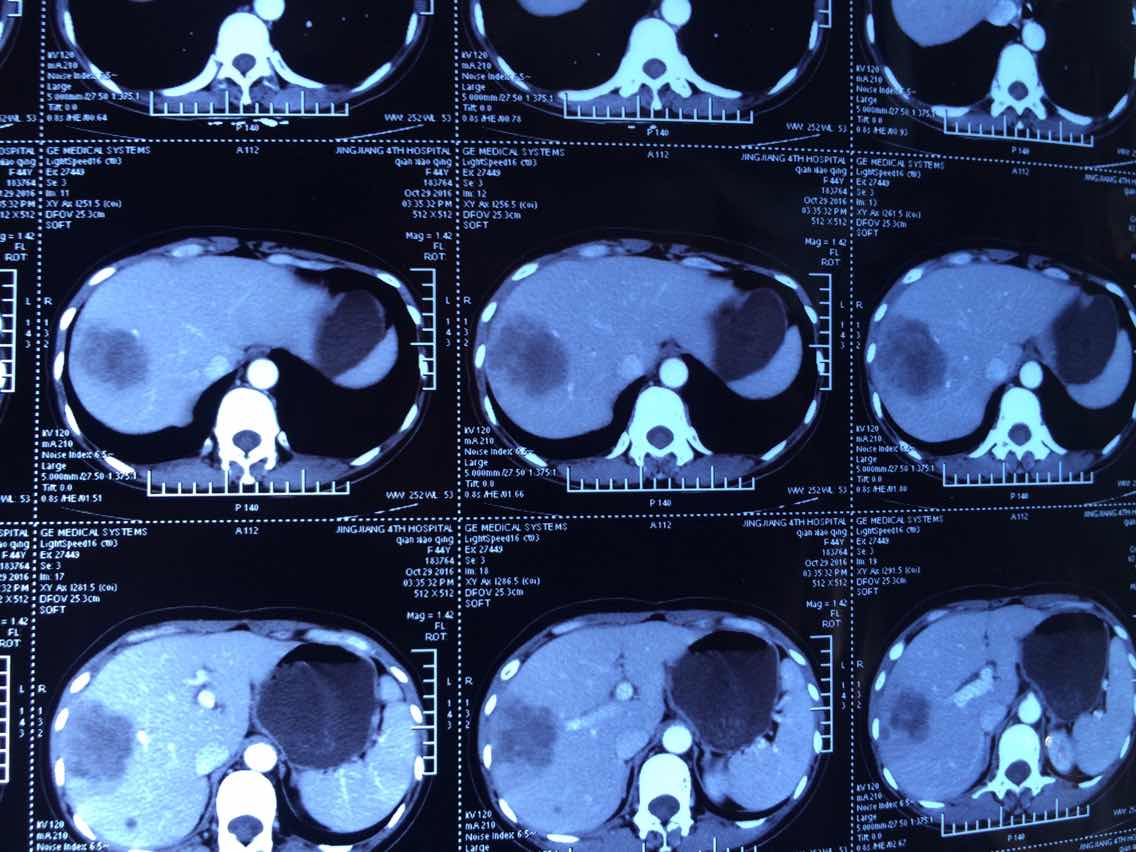

2

举报

2017-10-31 10:10:42 有用(0)

回复(0)

3

2017-10-31 10:11:05 有用(0)

2017.2.24的